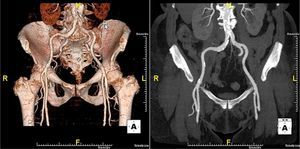

The patient was referred for aortic valve replacement surgery, but was refused on medical and surgical evaluation due to the high surgical risk (logistic EuroSCORE 22.3%). Percutaneous treatment was then considered, and anatomical assessment by transesophageal echocardiography and multidetector computed tomography showed this to be technically feasible. In particular, there was no significant iliofemoral arterial disease that would hinder access (Figure 2).